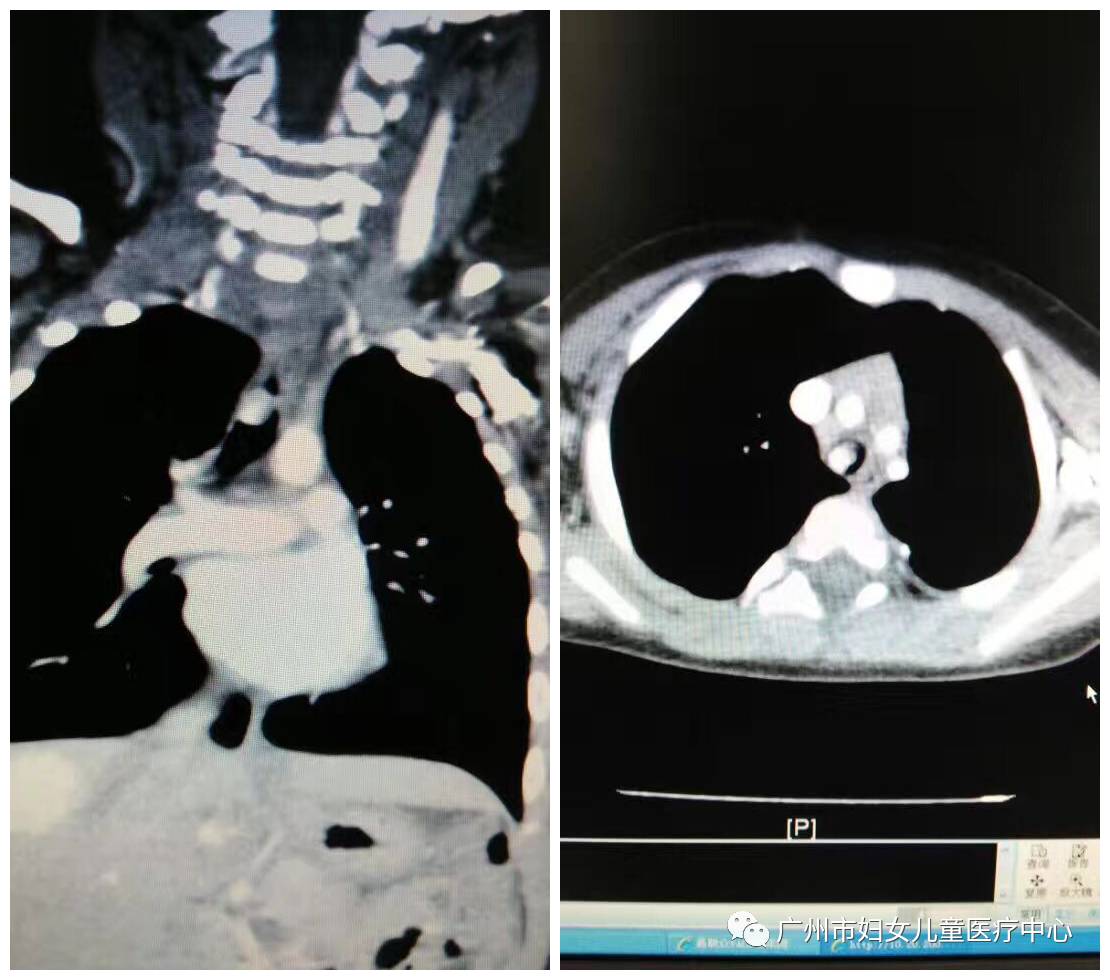

ECMO患儿术前CT显示:主气管占位及肝内血管瘤